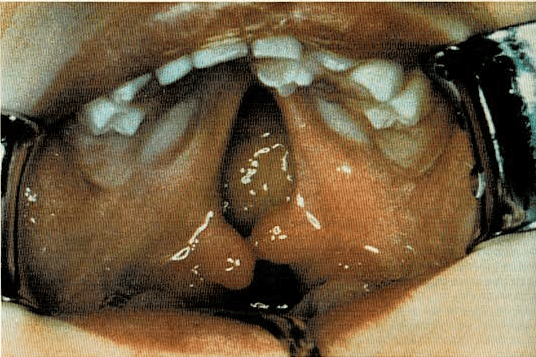

Fisura palatina

Es una abertura en el techo de la boca, que generalmente mantiene las cavidades bucal y nasal separadas. La abertura puede ser muy pequeña o por el contrario, tan grande que convierta ambas cavidades en una sola. Casi siempre la fisura se extiende al labio superior, además del paladar. En algunas ocasiones es hereditaria, pero lo más común es que algún proceso, antes del nacimiento del niño, interfiriera el desarrollo y soldadura normal de los mamelones que formarán la boca.

La fisura palatina es una hendidura del paladar (techo de la boca), de tipo congénito.

Se puedo arreglar por medio de una operación que une las dos partes de la fisura palatina.

El recién nacido con una fisura palatina puede tener dificultades para mamar y normalmente requerirá ser alimentado de forma particular. Además es de destacar que los niños con fisura palatina tienen tendencia a padecer infecciones del oído medio, por lo que precisan lavados cuidadosos efectuados a poca presión, a fin de evitar esta complicación.

El médico recomendará una operación correctora, que generalmente no se lleva a cabo hasta los dos años, o bien una prótesis dentaria, en lugar de la cirugía. El propósito es de dar buena apariencia a la cara del niño, capacitarle para mamar y hablar con normalidad y permitirle que tenga un desarrollo y crecimiento físico, emocional y social, normal.